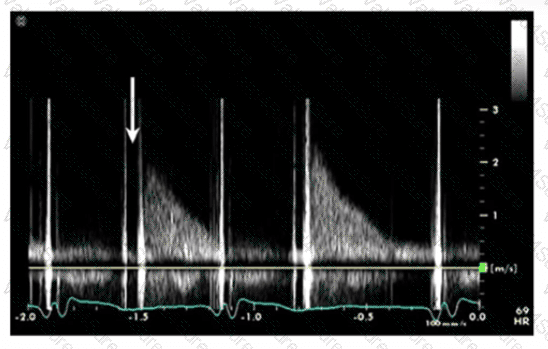

Which finding does peak mitral valve regurgitant Doppler velocity reflect?